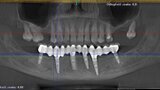

Natychmiastowa implantacja i zaopatrzenie protetyczne pacjentów z zaawansowaną chorobą przyzębia